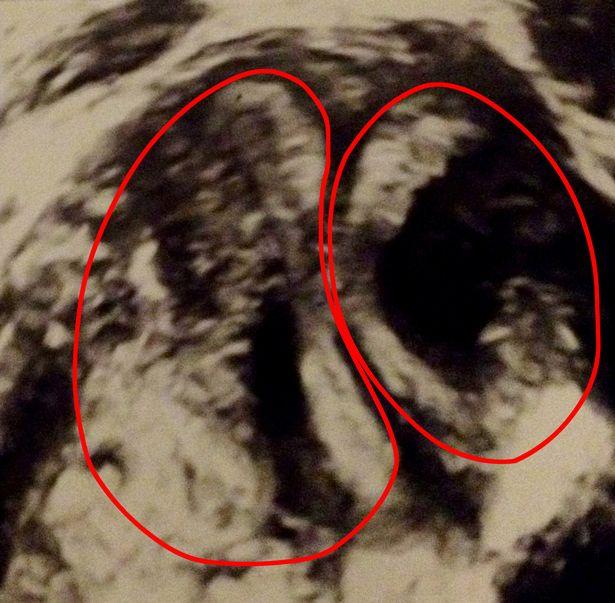

După ce a fost trimisă la Spitalul Prințesă Alexandra din Harlow, unde a fost efectuată o operație de descifrare a scanării, chirurgii au confirmat că Eleanor a avut două pântece, două coluri uiterine și două vagine.

Când mi s-a spus prima dată despre asta, eram doar foarte confuză. M-am gândit, cum aș fi putut trece prin viață și să nu știu? Mă bucur că am aflat când am făcut testul, deoarece asta însemna că sarcina mea ar putea fi monitorizată. Era doar un lucru atât de ciudat. Extern totul părea normal, cu un vagin care duce la un col uterin care duce la unul din pântece. Dar în interior am avut o duplicare a tuturor”.

Afecțiunea este cunoscută sub numele de didelphys uterin, o anomalie congenitală rară dezvoltată în timpul cănd esti făt, iar șansele de a avea această animalie sunt unu la un milion.